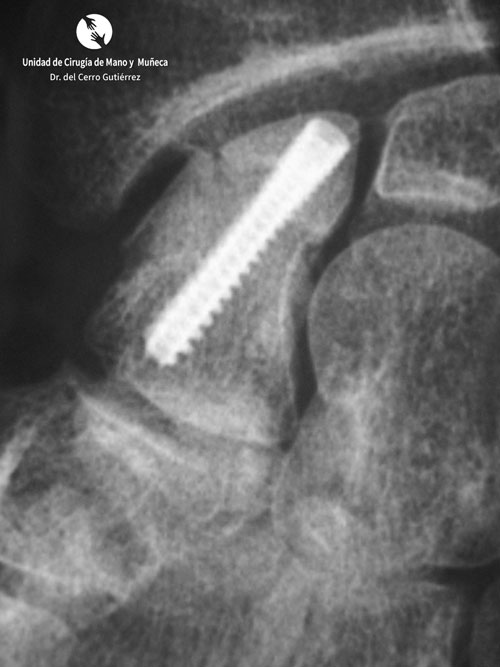

Fractura del Escafoides.Síntesis-Dorsal de Fractura

Síntesis Dorsal de Fractura

Fractura del Síntesis Percutánea Dorsal.